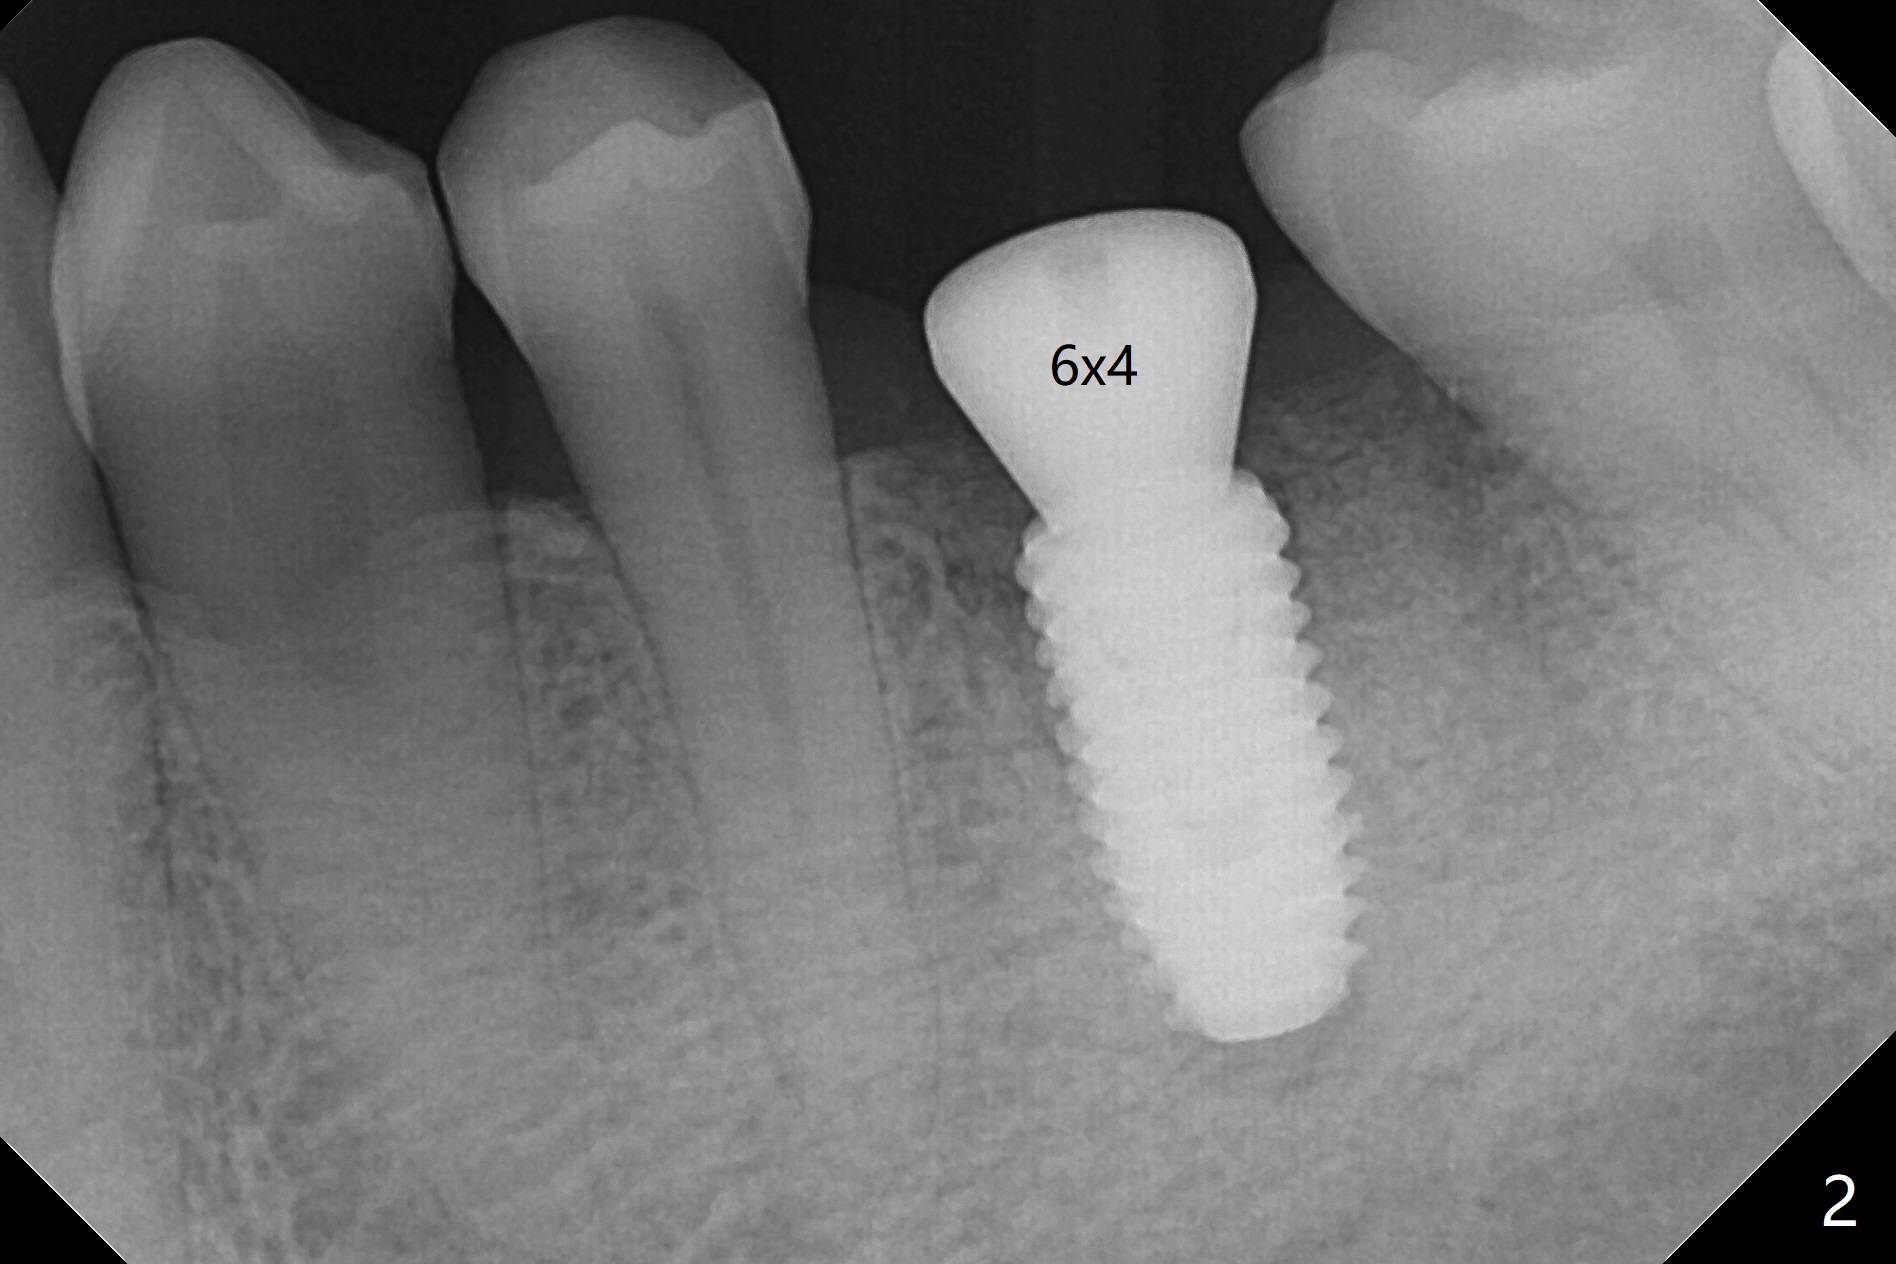

50来岁男,左下6位点保存术后4.5个月回来做导板植牙术,牙槽嵴和角化龈宽,几乎是最理想的手术。唯一担忧的是牙槽骨够不够硬(植骨后4.5个月),其实为了植入5毫米植体(图一),最后钻头必须4.5毫米,而且需要使用4.5毫米皮质骨功螺纹钻头,反复多次倒旋植体,最后扭力50Ncm,唯恐造成骨坏死。使用6毫米profile钻头后,放置6x4毫米基台,后者完全就位(图二,三)。术后病人汇报他根本感觉不到做过植牙术,以前做过徒手即刻植牙(30 13)。术后3.5月去除愈合基台,牙龈袖健康,使用Prosthetic treatment planning基台(没有六角形,容易就位,选择袖高度),放置修复基台(图四),拧紧20Ncm(厂家推荐30Ncm),放置plumber tape and Cavit,取模。口内粘固,事先牙冠(带有access hole)边缘涂凡士林,容易去除残余粘固剂,争取不取出基台,减少牙龈附着破坏。